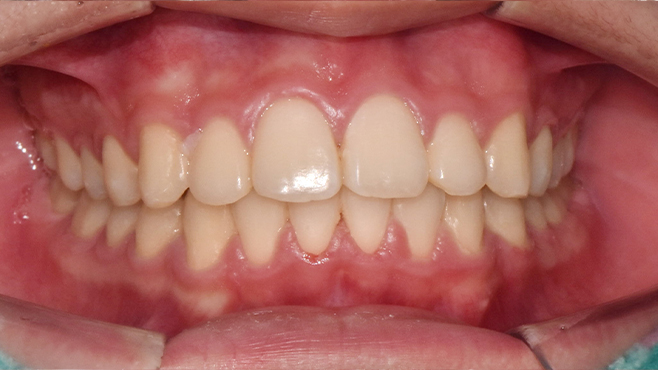

맞는 건 괜찮은데… 충치는 못 참겠습니다|20대 격투기 선수 치과 방문기